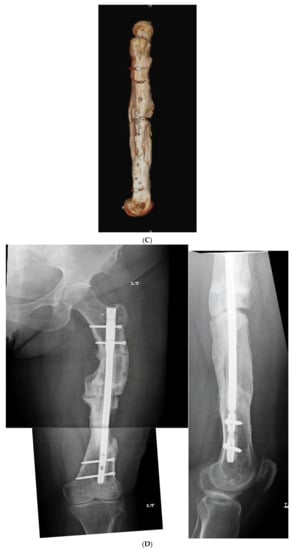

Figure 8.

(A) Adult male with varus malunion deformity after a prior tibia fracture and nailing. (B,C) Patient underwent focal dome osteotomy with compression nailing using a magnetic motorized nail for early and subsequent nail compression. (D) Patient declined to follow-up after 12 weeks, citing absence of pain. Patient returned at 6 months at request of surgeon, still without pain. Magnetic nail recompressed. Patient lost to follow-up after 6 months.